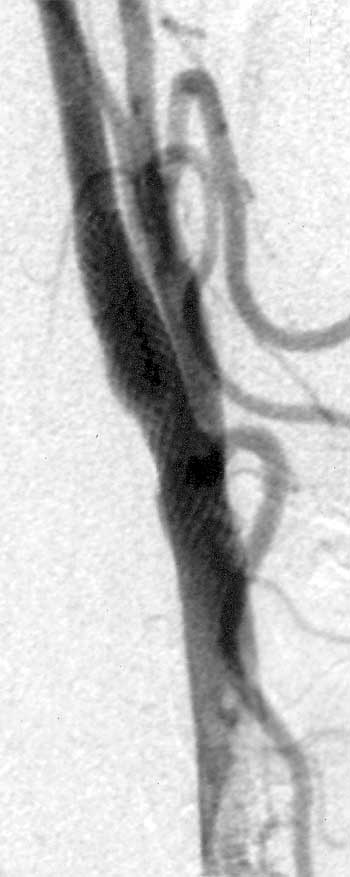

Ballondilatation und Stenting einer hochgradigen Karotisstenose

| Vor Therapie | Stent platziert | Nach Dilatation |